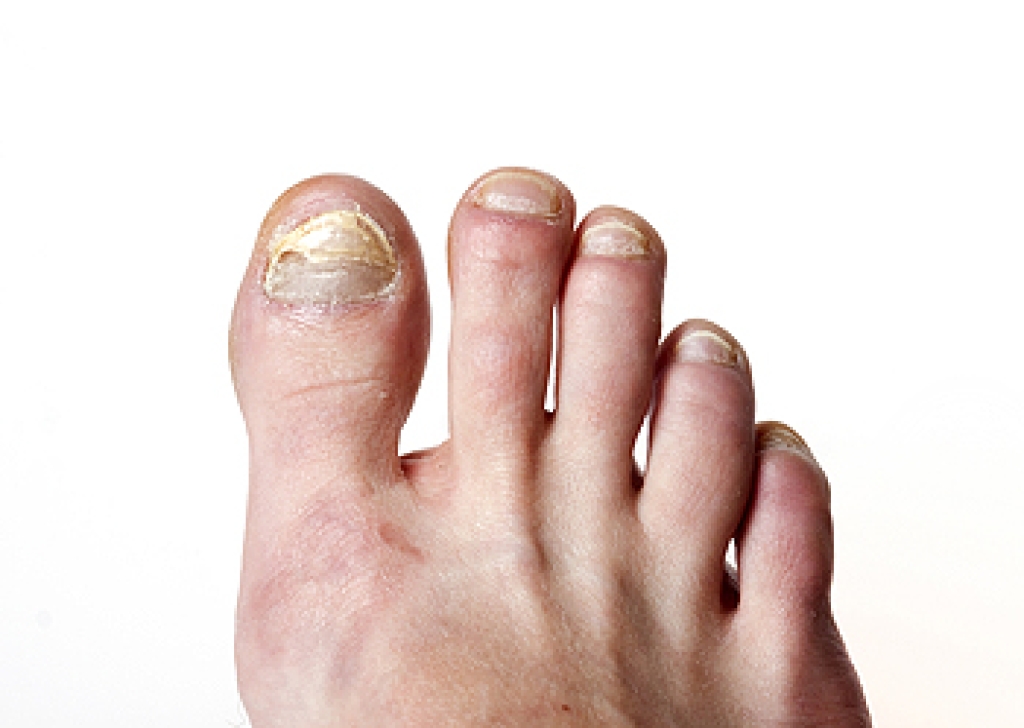

Thick toenails can develop for several reasons, and understanding the cause helps guide proper treatment. One of the most frequent reasons is a fungal infection, which can make the nail appear yellow, brittle, and difficult to trim. Repeated trauma from wearing tight shoes or stubbing the toe can also cause the nail to thicken as it tries to protect itself. Aging naturally slows nail growth and can change texture over time. In some cases, medical conditions such as psoriasis or poor circulation may contribute to nail thickening. A podiatrist can identify the cause through examination and testing, then recommend the right treatment, which may include antifungal medication, nail debridement, or improved footwear. If your toenails have become thick, painful, or hard to manage, it is suggested that you seek care from a podiatrist to restore nail health and prevent future problems.

If left untreated, toenail fungus may spread to other toenails, skin, or even fingernails. If you suspect you have toenail fungus it is important to seek treatment right away. For more information about treatment, contact one of our podiatrists of Prince William Foot & Ankle Center, PC. Our practitioners can provide the care you need to keep you pain-free and on your feet.

Symptoms

- Warped or oddly shaped nails

- Yellowish nails

- Loose/separated nail

- Buildup of bits and pieces of nail fragments under the nail

- Brittle, broken, thickened nail